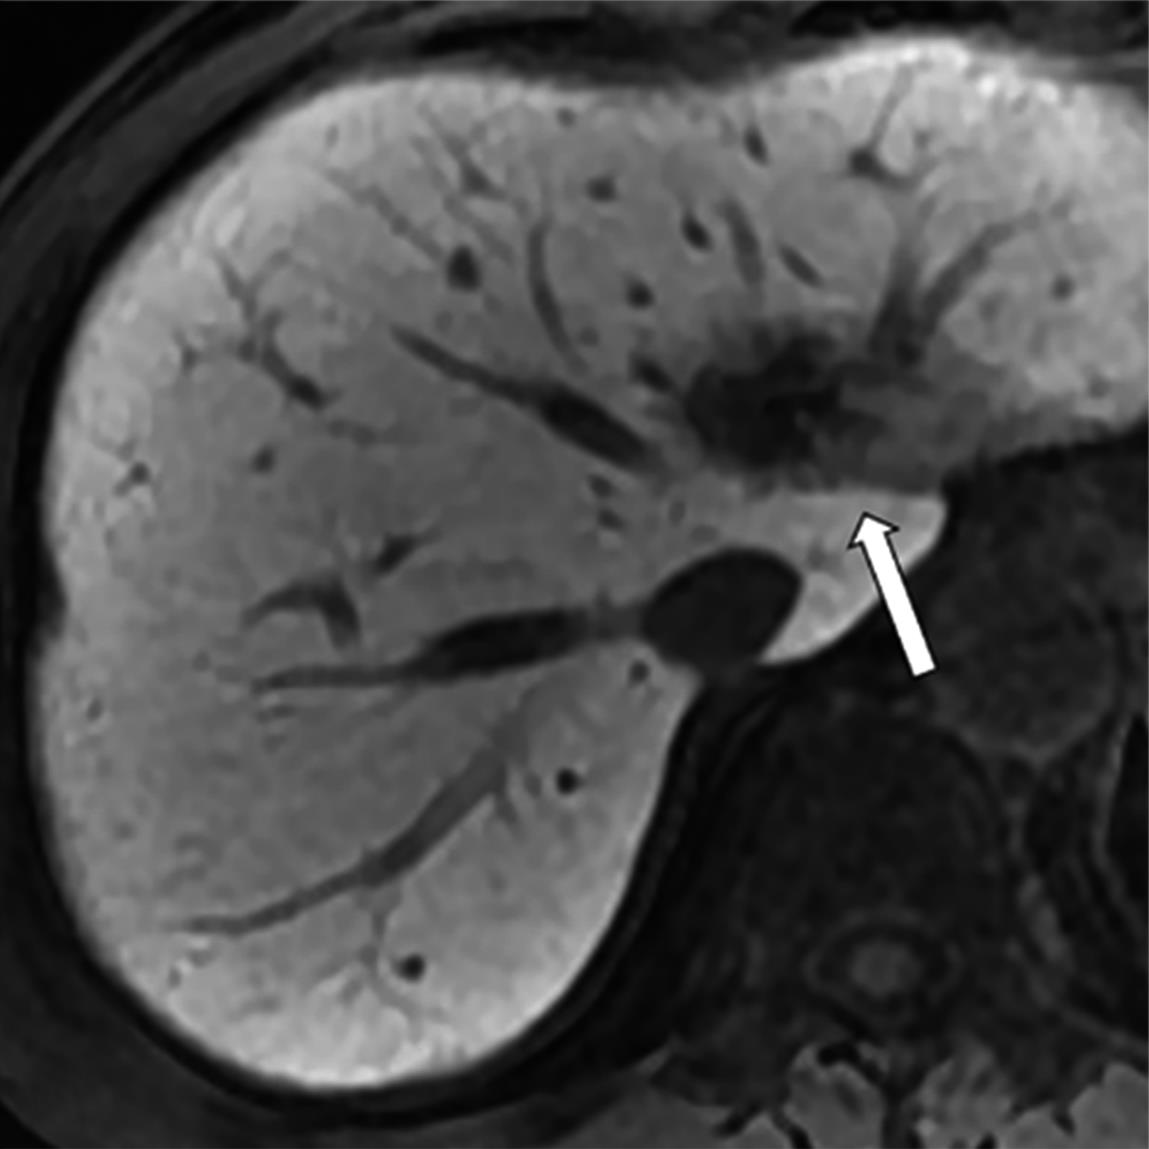

• MRI瘤周特征在预测结直肠癌肝转移非解剖性肝切除术预后的价值

摘要:目的 研究结直肠肝转移(colorectal liver metastases,CRLM)瘤周影像特征在非解剖切除(non-anatomic resection,NAR)后CRLM患者中长期预后的价值。方法 回顾性纳入术前行腹部钆塞酸二钠增强磁共振成像(magnetic resonance imaging,MRI)和NAR术后的CRLM患者。影像特征评估动脉期瘤周高强化、肝胆期(hepatobiliary phase,HBP)瘤周低摄取和瘤周胆管扩张。应用Kaplan-Meier法计算生存率,并采用Cox比例风险回归模型进行单因素和多因素分析以确定无肝内复发生存期(liver recurrence-free survival,LRFS)、无复发生存期(recurrence-free survival,RFS)和总生存期(overall survival,OS)的独立预测因素。结果 本研究共纳入36例患者,58个CRLM病灶。存在和不存在动脉期瘤周高强化的患者3年LRFS和RFS率有统计学差异(LRFS:14.3% vs. 43.9%,P=0.005;RFS:14.3% vs. 40.3%,P=0.006)。动脉期瘤周高强化与较差的LRFS(P=0.002,HR=5.541,95%CI=1.853~15.975)和较差的RFS(P=0.002,HR=5.392,95%CI=1.887~15.412)独立相关。胆管扩张和HBP瘤周低摄取均不为LRFS、RFS和OS的独立预测因素。结论 动脉期瘤周高强化是接受NAR的CRLM患者LRFS和RFS预后因子。